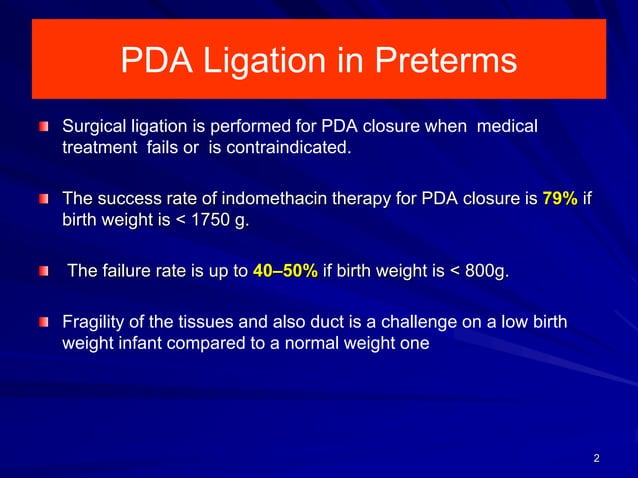

Surgical closure Neonatal PDA PPT

Text Patent Ductus Arteriosus PDA in Premature Infants

PATENT DUCTUS ARTERIOSUS PDA IN CHILDREN Dr Gaurav Agrawal

PDA in Preterm Infants Neonatal Network South East

25 PDA in preterm infants 75 PATENT DUCTUS ARTERIOSUS IN PRETERM